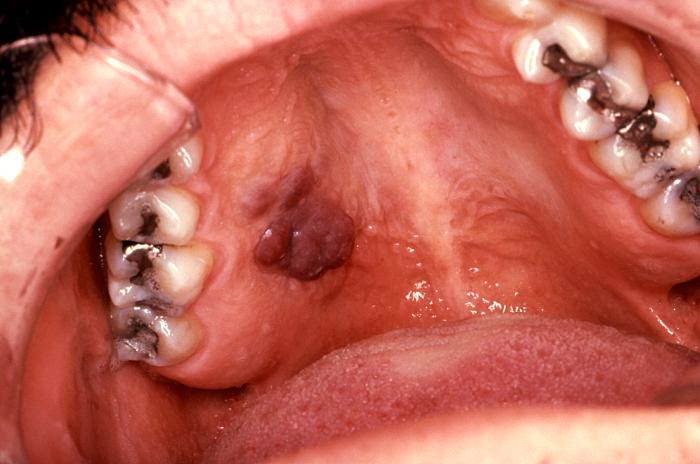

El sarcoma Kaposi es la neoplasia

intraoral más común que se observa en el SIDA y generalmente se presenta en

el paladar duro, encías y zona del trígono retromolar, como una mancha violácea o

rojiza, de límite difuso, indolora, que en el 20% de los casos puede ser la

primera manifestación.

Sarcoma de Kaposi

en paladar duro |